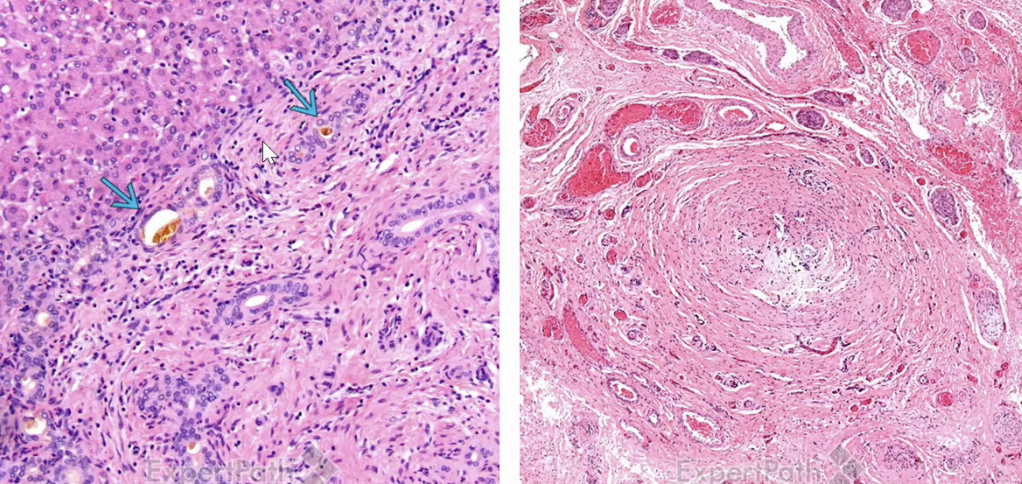

Choledochal Cyst

a congenital dilatation of the bile duct that can lead to complications such as cholangitis and pancreatitis - even when removed predisposes to cancer

Extrahepatic Cholangiocarcinoma

Klatskin Tumor

A type of extrahepatic cholangiocarcinoma that occurs at the junction of the left and right hepatic ducts. It often leads to biliary obstruction and jaundice.